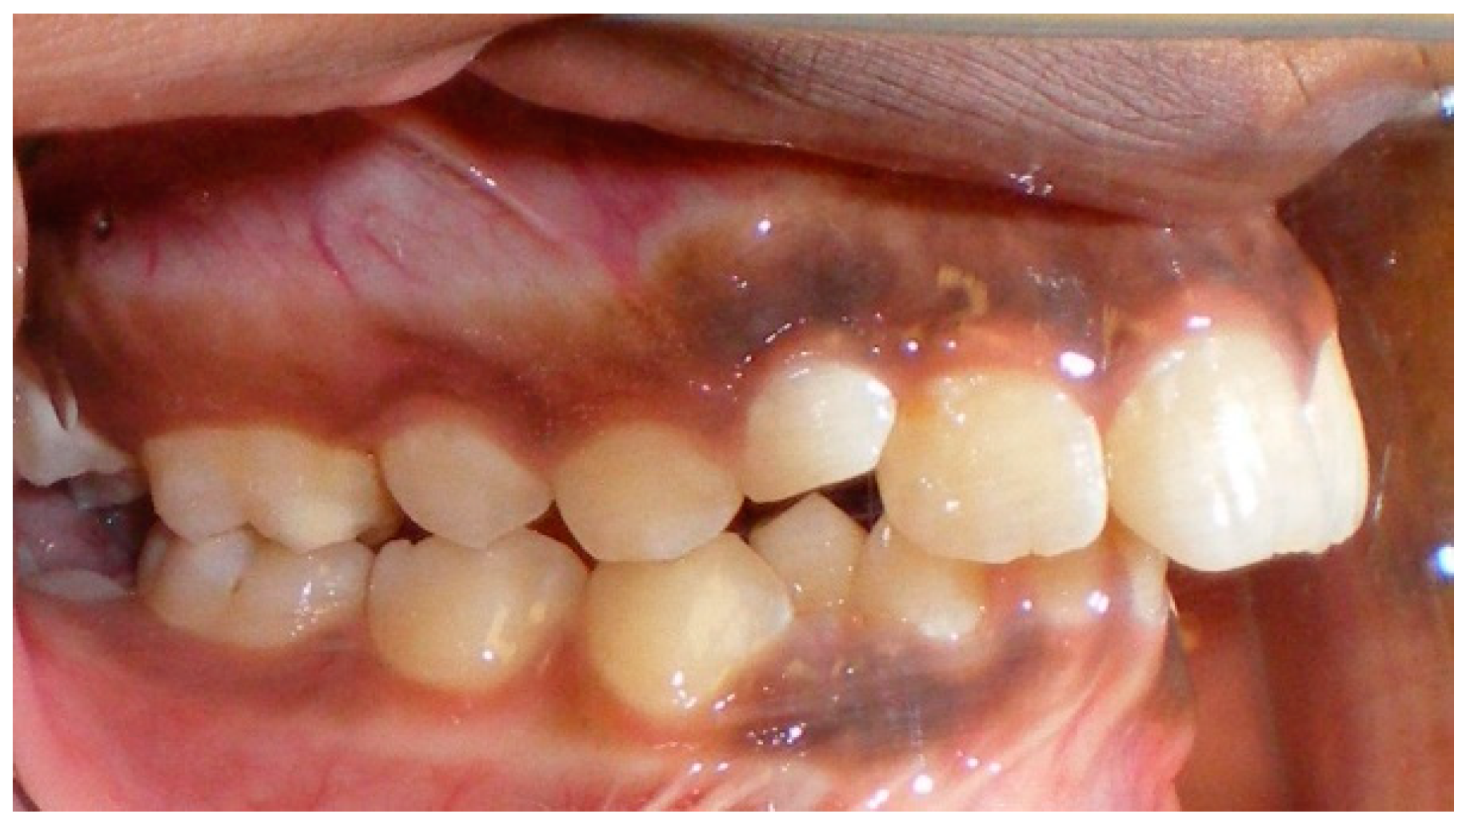

- Assessment of proposed sites of temporary anchorage device (TAD). Figure 11, Figure 12, Figure 13 and Figure 14 show correction of the Class II molar relationship using a temporary anchorage device. Figure 11 shows a pre-treatment intraoral photograph of the right side. The Class II molar relationship can be observed. Figure 12 shows coronal, sagittal and axial views, as well as a volume rendering of CBCT that was acquired in order to assess the site of the temporary anchorage device. Figure 13 shows an intraoral photograph of the right side, in which the TAD was placed mesial to the maxillary first molar, and a power chain was attached from this TAD to a hook placed distal to the lateral incisor. Figure 14 shows a post-treatment intraoral photograph showing improvement of the Class II molar relationship after removal of all orthodontic appliances.